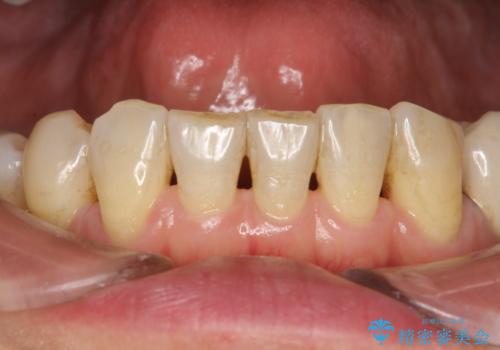

- 定期的にメンテナンスにいらしている方です。特にお変わりないとのことでPMTC60分コースで全体的なクリーニングを行いました。